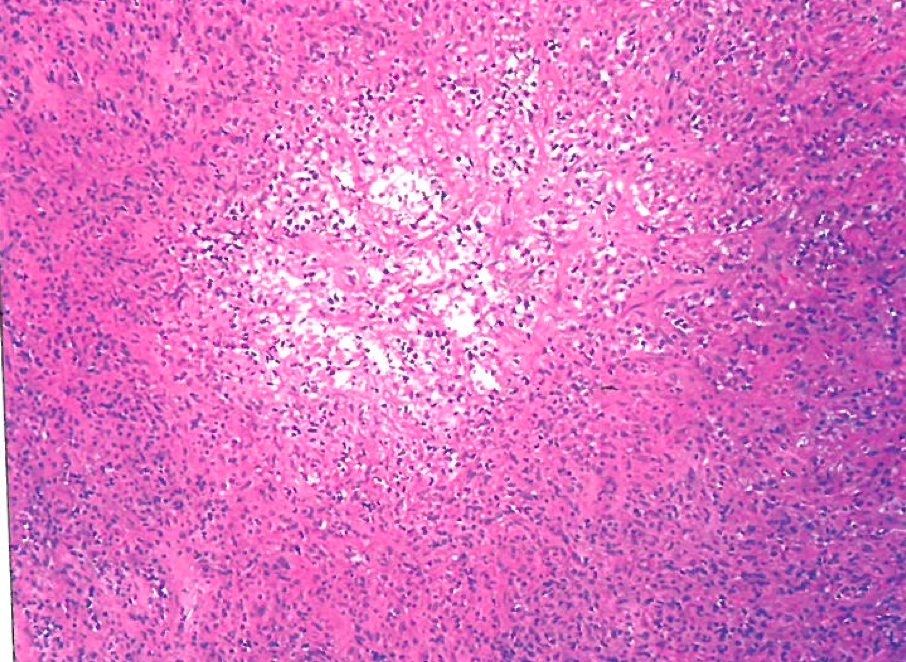

Mycobacterium tuberculosis

Important Mycobacterial species in the lymph node

MAC, M TB, M scrofulaceum, M haemophilum